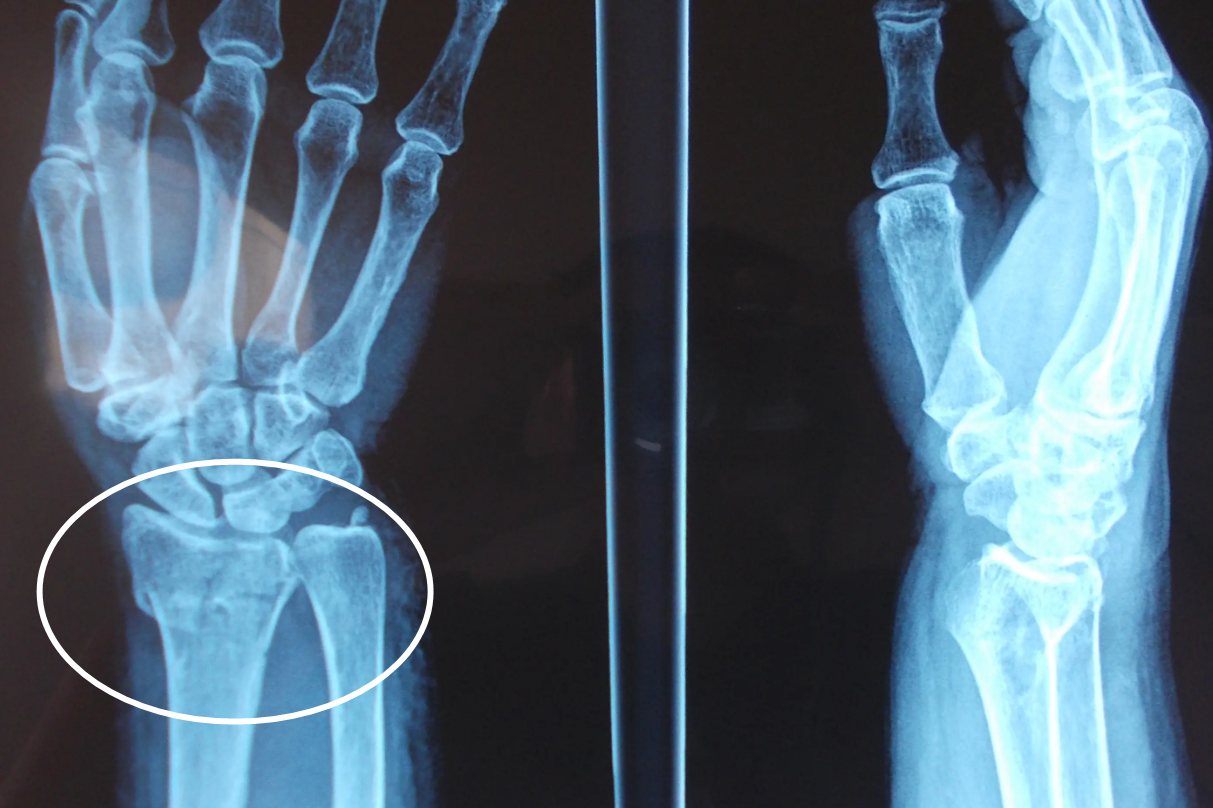

克雷氏骨折具有典型的骨折畸形,正面观可见“刺刀样”畸形同时侧面观可见“银叉样”畸形,骨折移位明显。在X光片下可以看见骨折近端向掌侧移位,远端向桡、背侧移位。除了典型的畸形还有骨折的常见特征,腕关节部位出现明显的疼痛感觉,并且活动受限。当伴随神经损伤或压迫时,手部感觉会出现异常。